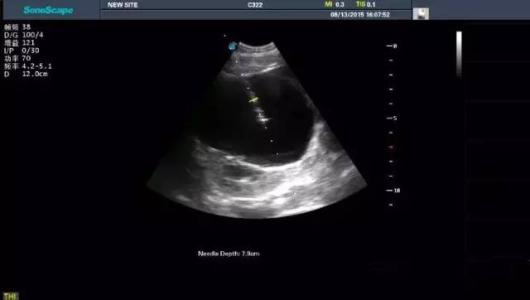

擅长:腹部、妇产超声诊断,小器官、胃肠疾病超声诊断,疑难重症超声诊断,超声造影、超声介入治疗... 查看详情

擅长:熟练掌握心血管、腹部和浅表脏器的超声诊断技术,在心血管,腹部、妇产科疾病以及小脏器等... 查看详情